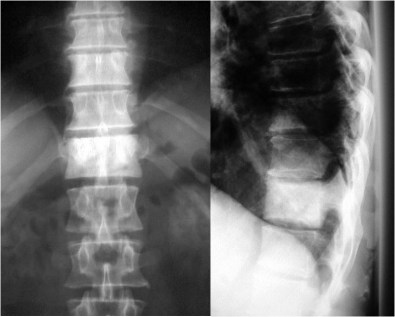

SIGNO DE LA C

Signo de coalición subtalar (fusión calcáneo-astragalina) en la radiografía lateral del tobillo. La «C» se forma por el límite medial de la cúpula talar y el límite posteroinferior del sustentaculum tali.

En la radiografía lateral de tobillo hemos marcado con flechas la «C» que da nombre al signo.

La fusión calcáneo-astragalina (flecha) se comprueba en el corte coronal de TC de tobillo.